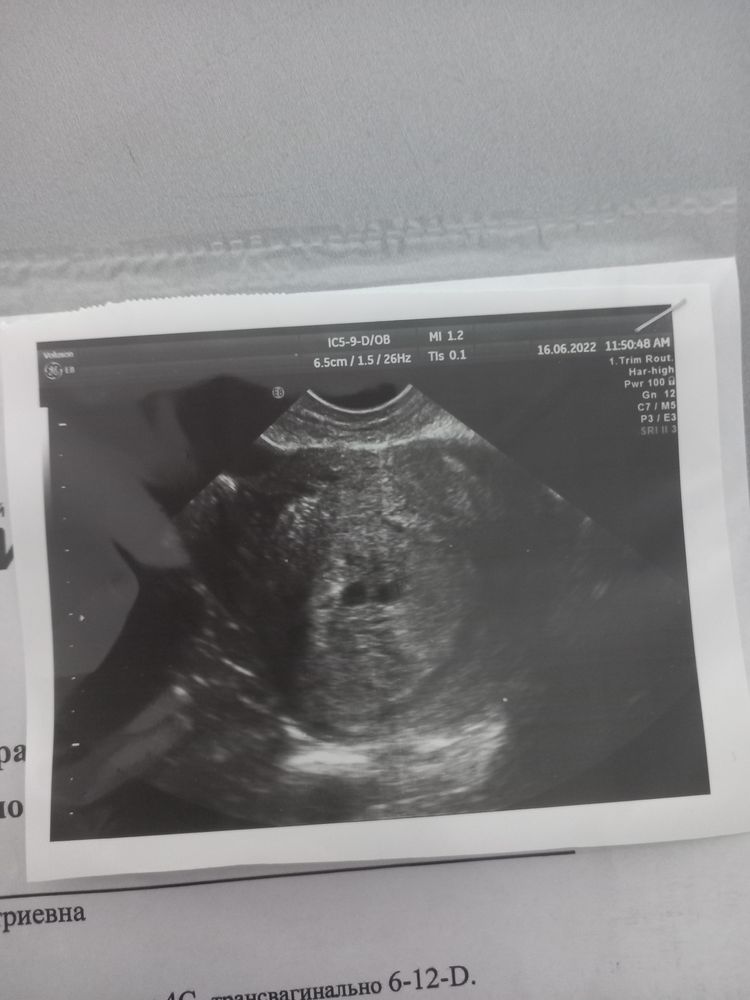

Может на этом сроке это было желтое тело или гематома?

Тамара В, все может быть но хгч 646 на второй день задержки указывал на двойню.

Антенатальная гибель одного малыша Маловодие 1 плода при многоплодной беременности